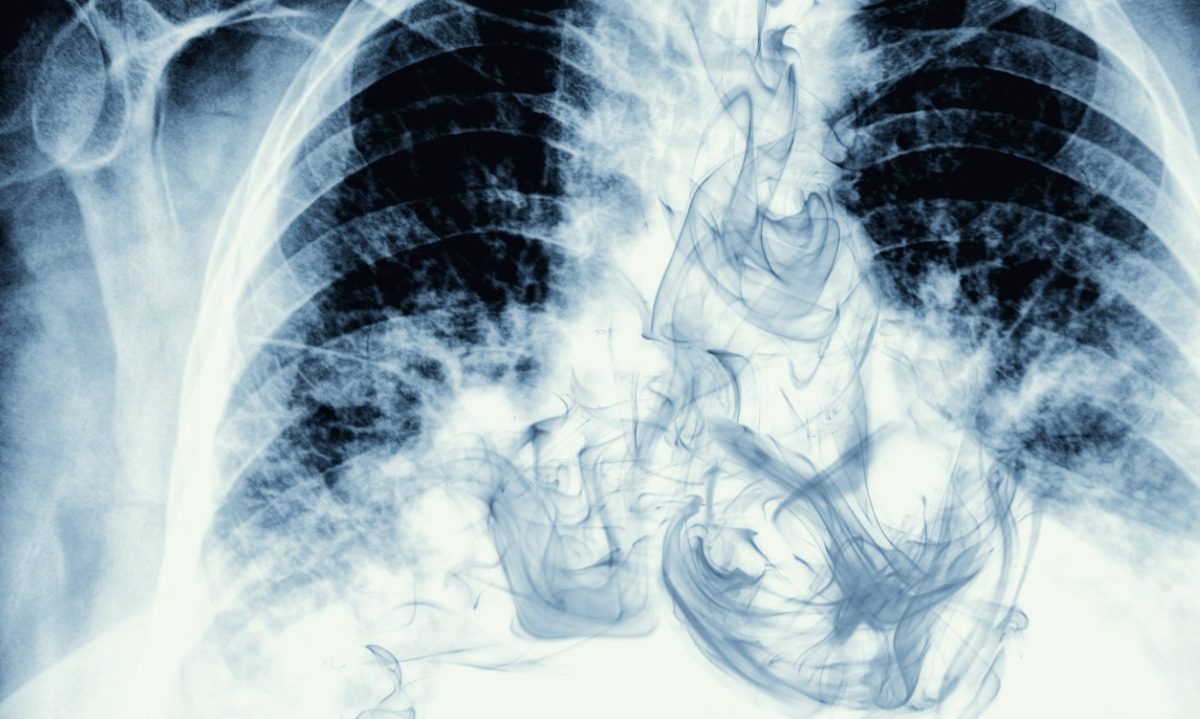

Το άτμισμα καλύπτει τους πνεύμονες με δυνητικά επιβλαβείς χημικές ουσίες. Τα παρασκευάσματα ηλεκτρονικών υγρών συνήθως περιλαμβάνουν κάποιο μείγμα από γεύσεις, αρωματικά πρόσθετα και νικοτίνη ή THC (η χημική ουσία στη μαριχουάνα που προκαλεί ψυχολογικά αποτελέσματα), διαλυμένη σε μια ελαιώδη υγρή βάση. “Πιστεύουμε ότι ορισμένα από τα εξατμισμένα στοιχεία του λαδιού εισχωρούν βαθιά στους πνεύμονες και προκαλούν μια φλεγμονώδη απόκριση”, εξηγεί ο δρ. Broderick.

Πώς το άτμισμα μπορεί να επηρεάσει τους πνεύμονες

Με την πάροδο του χρόνου, καθώς η χρήση του ηλεκτρονικού τσιγάρου συνεχίζεται, οι ειδικοί θα κατανοήσουν καλύτερα πώς το άτμισμα επηρεάζει τους πνεύμονες. Αυτό που γνωρίζουμε αυτήν τη στιγμή είναι ότι πολλές ασθένειες των πνευμόνων σχετίζονται με το άτμισμα: